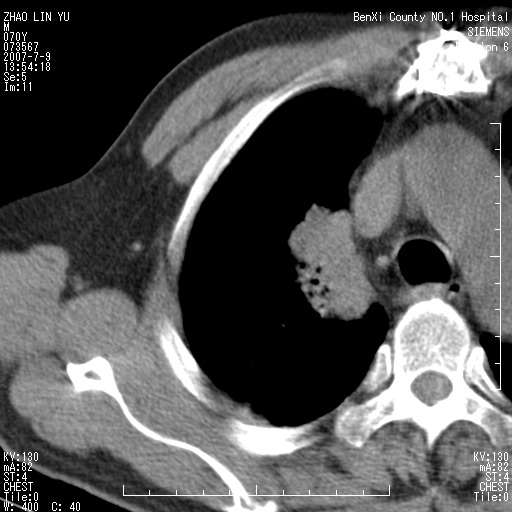

以下是引用王靖旗在2007-7-10 17:12:00的发言:[br] 男、70、咳嗽两个月,半年前换瓣手术,胸片未见异常,于昨天行x片发现右肺上野大片影,行ct扫描,这里是减薄图像,余肺正常。明天晚上会有增强扫描片,到时我会上传。[br][br] 冠状位请大家细看,应该是有意义的,[br][br] 请大家先看平扫发表意见。[br][br]

以下是引用zhangzhongshou在2007-7-10 21:43:00的发言:[br]右肺上叶周围型肺癌,以孤立型细支气管肺泡癌可能性大。